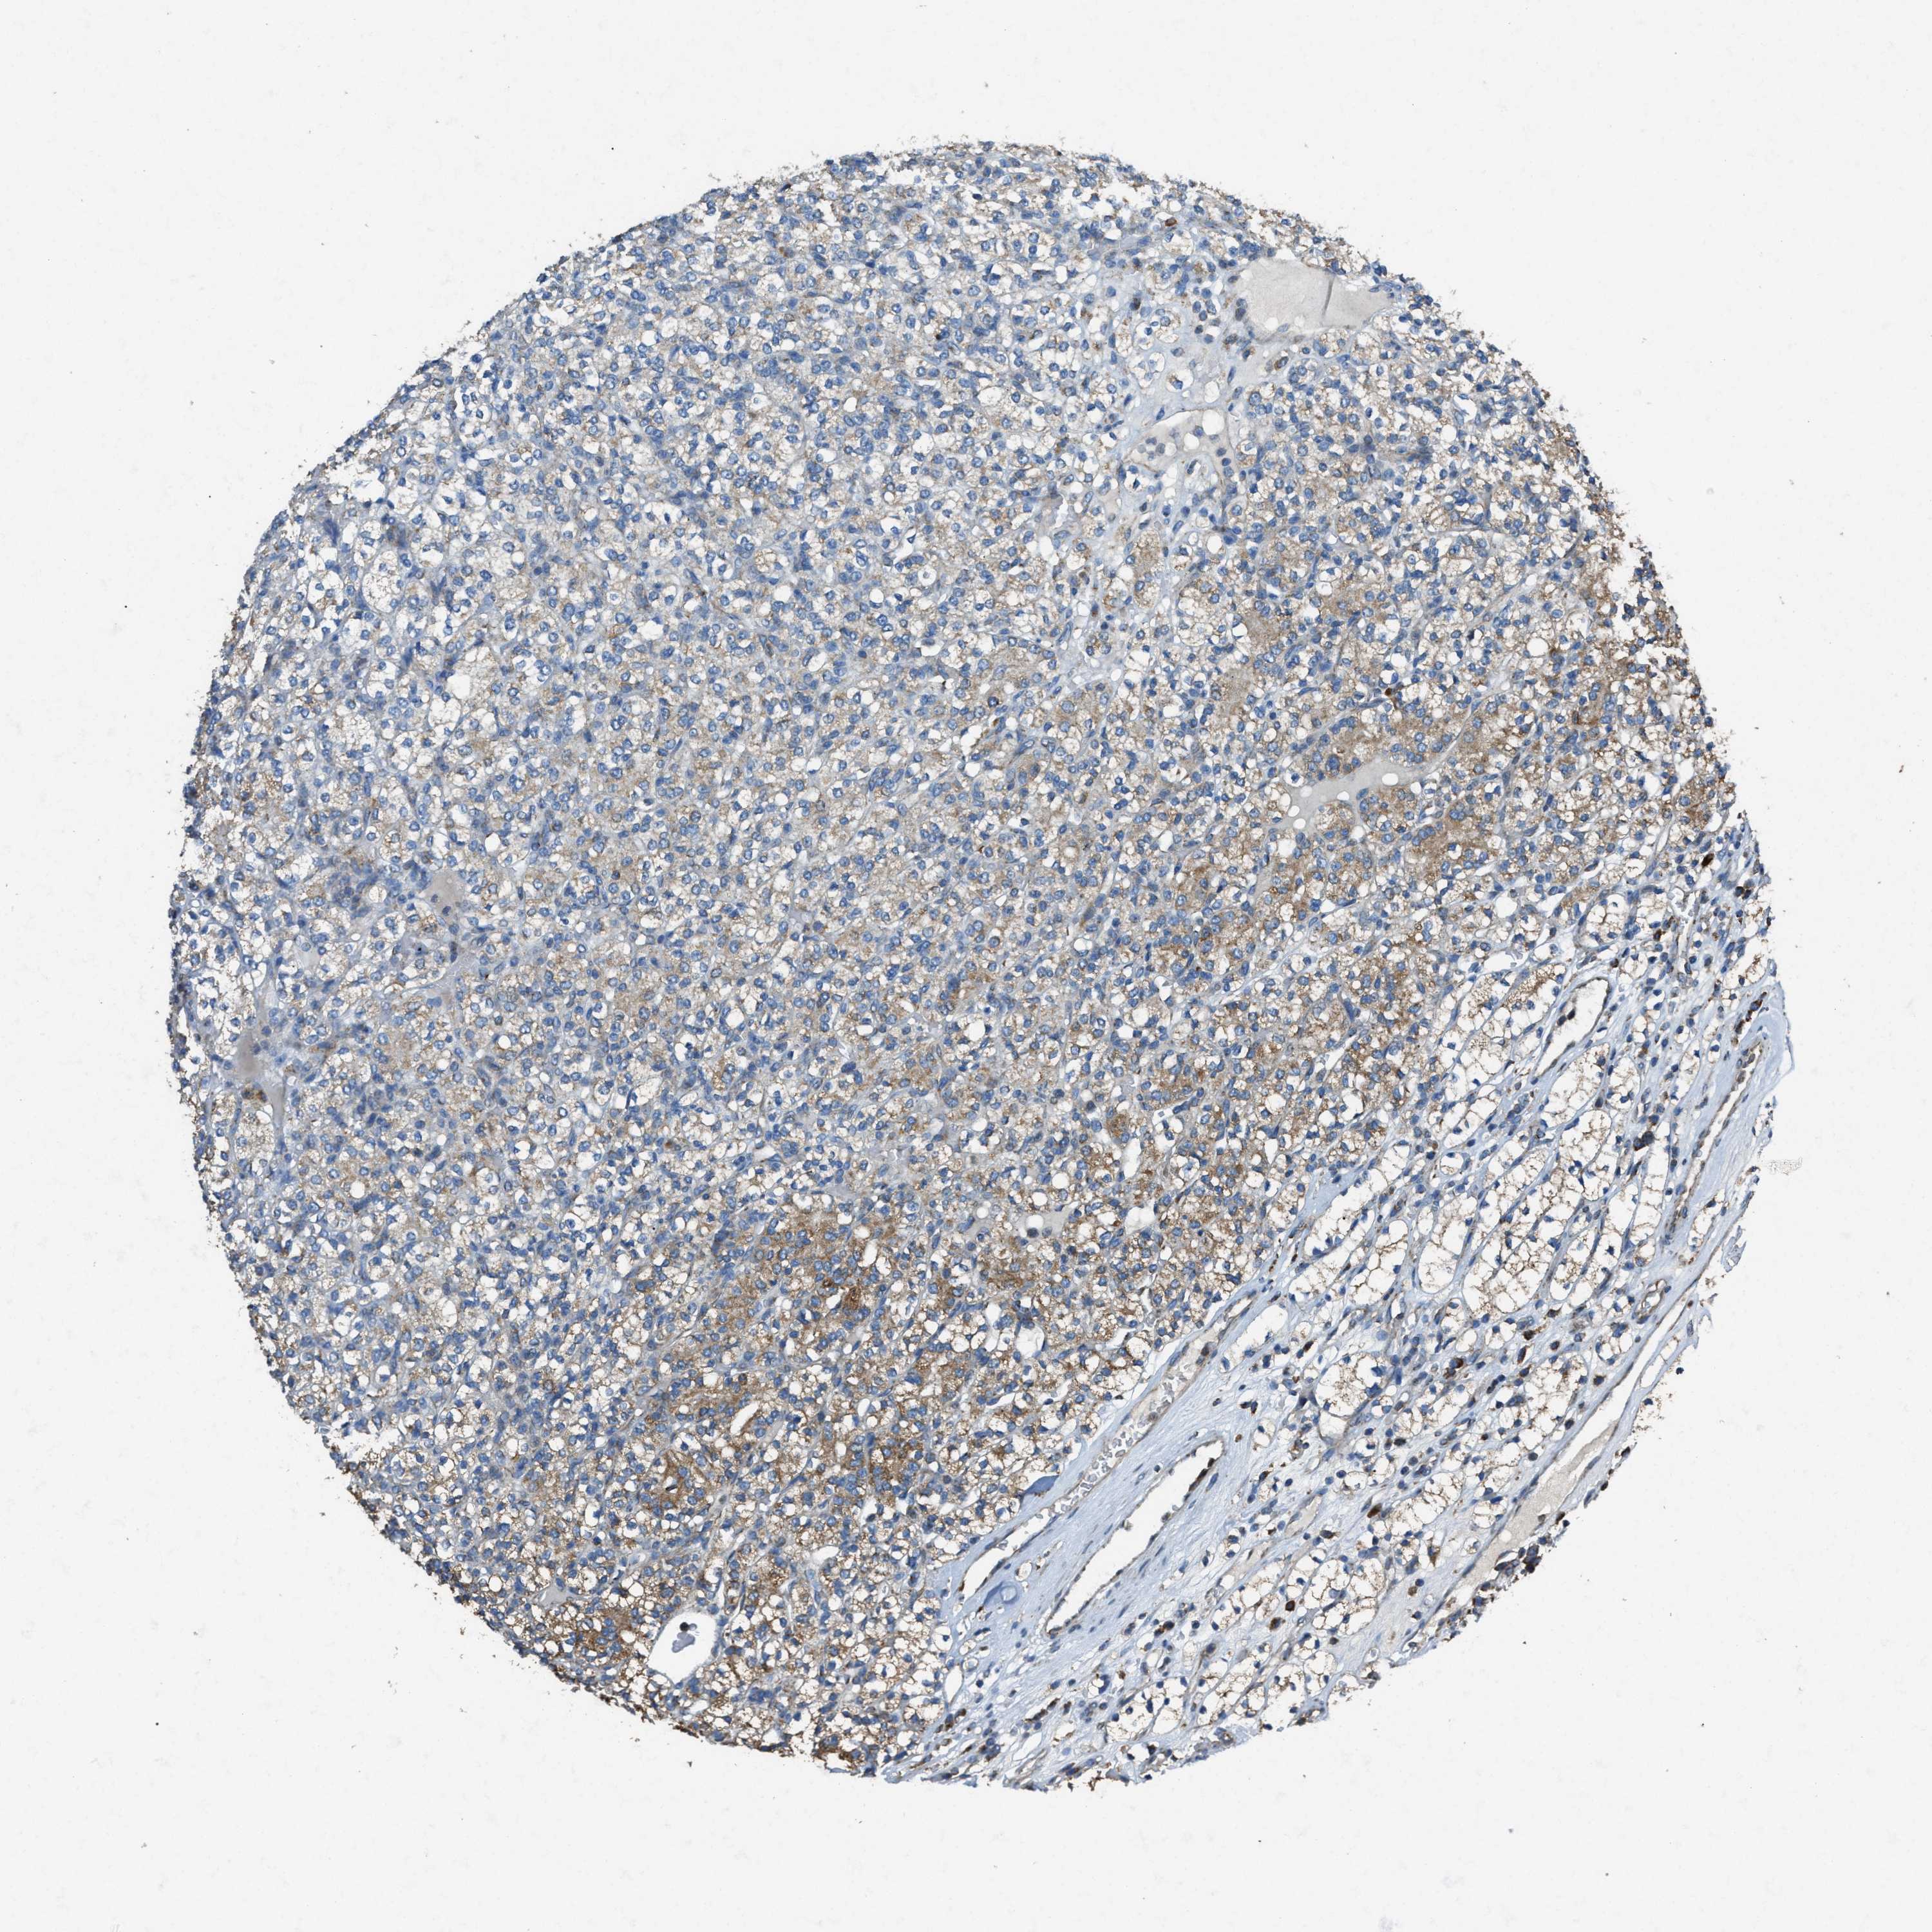

KIDNEY RENAL CLEAR CELL CARCINOMA (TCGA) - Interactive survival scatter ploti

The Survival Scatter plot shows the clinical status (i.e. dead or alive) for all individuals in the patient cohort, based on the same data that underlies the corresponding Kaplan-Meier plots. Patients that are alive at last time for follow-up are shown in blue and patients who have died during the study are shown in red.

The x-axis shows the expression levels (FPKM) of the investigated gene in the tumor tissue at the time of diagnosis. The y-axis shows the follow-up time after diagnosis (years). Both axes are complimented with kernel density curves demonstrating the data density over the axes. The top density plot shows the expression levels (FPKM) distribution among dead (red) and alive patients (blue). The right density plot shows the data density of the survived years of dead patients with high and low expression levels respectively, stratified using the cutoff indicated by the vertical dashed line through the Survival Scatter plot. This cutoff is automatically defined based on the FPKM cutoff that minimizes the p-score. The cutoff can be changed by dragging the vertical line or by entering a cutoff value in the square labeled "Current cut-off".

Under the Survival Scatter plot the p-score landscape (black curve; left axis) is shown together with dead median separation (red curve; right axis). Dead median separation is the difference in median mRNA expression between patients who have died with high and low expression, respectively. It is calculated as follows: median FPKM expression of dead patients with high expression - median FPKM expression of dead patients with low expression. This is intended to aid the user in visually exploring custom cutoffs and the associated p-scores and dead median separation.

Individual patient data is displayed and can be filtered by clicking on one or more of the category buttons on the top of the page. Categories describing expression level and patient information include: high, low, alive, dead, female, male and tumor stages. The scale of the x-axis can be toggled between linear and log-scale by clicking on the "x log" button. Mouse-over function shows TCGA ID, patient information and mRNA expression (FPKM) for each patient.

& Survival analysisi

Kaplan-Meier plots summarize results from analysis of correlation between mRNA expression level and patient survival. Patients were divided based on level of expression into one of the two groups "low" (under cut off) or "high" (over cut off). X-axis shows time for survival (years) and y-axis shows the probability of survival, where 1.0 corresponds to 100 percent.

SLC25A11 is potential prognostic, high expression is favorable in Kidney Renal Clear Cell Carcinoma (TCGA)

Best expression cut offi

Based on the FPKM value of each gene, patients were classified into two groups and association between prognosis (survival) and gene expression (FPKM) was examined. The best expression cut-off refers the FPKM value that yields maximal difference with regard to survival between the two groups at the lowest log-rank P-value. Best expression cut-off was selected based on survival analysis .

When clicking on this number, the vertical dashed line indicating cut-off, the interactive survival plot, and the Kaplan-Meier curve will be adjusted to show results based on the best expression cut-off.

: 65.5

TCGA RNA samplesi

RNA-seq data is reported as average FPKM (number Fragments Per Kilobase of exon per Million reads), generated by the The Cancer Genome Atlas (TCGA) .

Normal distribution across the dataset is visualized with box plots, shown as median and 25th and 75th percentiles. Points are displayed as outliers if they are above or below 1.5 times the interquartile range. FPKM values of the individual samples are presented next to the box plot.

Average pTPM 72.9

Number of samples 521